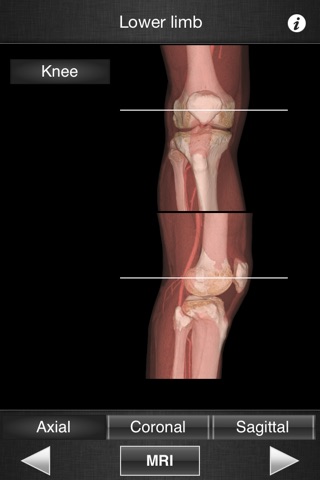

It only contains knee images.

This application is designed for healthcare professionals (Radiologists, General Practitioners, Orthopedists, Surgeons, Physiotherapists among others) as well for students, as a reference and learning tool. It contains 82 contiguous knee MR slices (4-5 mm thickness) in the three anatomical planes.

- 3D Image volume (VR) allows precise location of slice position.